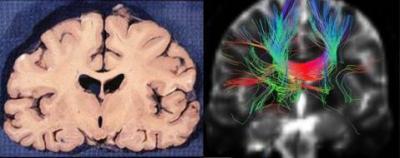

At present, fiber tracking algorithms are divided into deterministic tractography and probabilistic tractography. In deterministic algorithms, scholars proposed the fiber assignment by continuous tracking algorithm, the tensor deflection algorithm, the tensorline algorithm. Deterministic algorithms track fibers mainly depending on diffusion direction; however, they are susceptible to noise and partial volume effects, which result in the accumulation of tracking errors. Probabilistic algorithms can effectively reduce noise and partial volume effects, thus decreasing the accumulated errors and providing more fiber orientations. Unfortunately, their calculations are very complicated, time-consuming and easy to produce additional ambiguous fibers, which make the application of these algorithms difficult. In response to these phenomena, Shan Jiang and colleagues from School of Mechanical Engineering, Tianjin University proposed the tri-linear interpolation algorithm for white matter fiber tracking. A recent study from Jiang et al, published in the Neural Regeneration Research (Vol. 8, No. 23, 2013), selected a patient with acute infarction of the right basal ganglia and designed experiments based on either the tri-linear interpolation algorithm or tensorline algorithm. Fiber tracking in the same regions of interest (genu of the corpus callosum) was performed separately. The validity of the tri-linear interpolation algorithm was verified by quantitative analysis, and its feasibility in clinical diagnosis was confirmed by the contrast between tracking results and the disease condition of the patient as well as the actual brain anatomy. Statistical results showed that the maximum length and average length of the white matter fibers tracked by the tri-linear interpolation algorithm were significantly longer. The tracking images of the fibers indicated that this method can obtain smoother tracked fibers, more obvious orientation and clearer details. Tracking fiber abnormalities are in good agreement with the actual condition of patients, and tracking displayed fibers that passed though the corpus callosum, which was consistent with the anatomical structures of the brain. Therefore, the tri-linear interpolation algorithm can achieve a clear, anatomically correct and reliable tracking result.

Comparison between coronal anatomy and fiber tracking results of the patient with cerebral infarction.

(Photo Credit: Neural Regeneration Research)